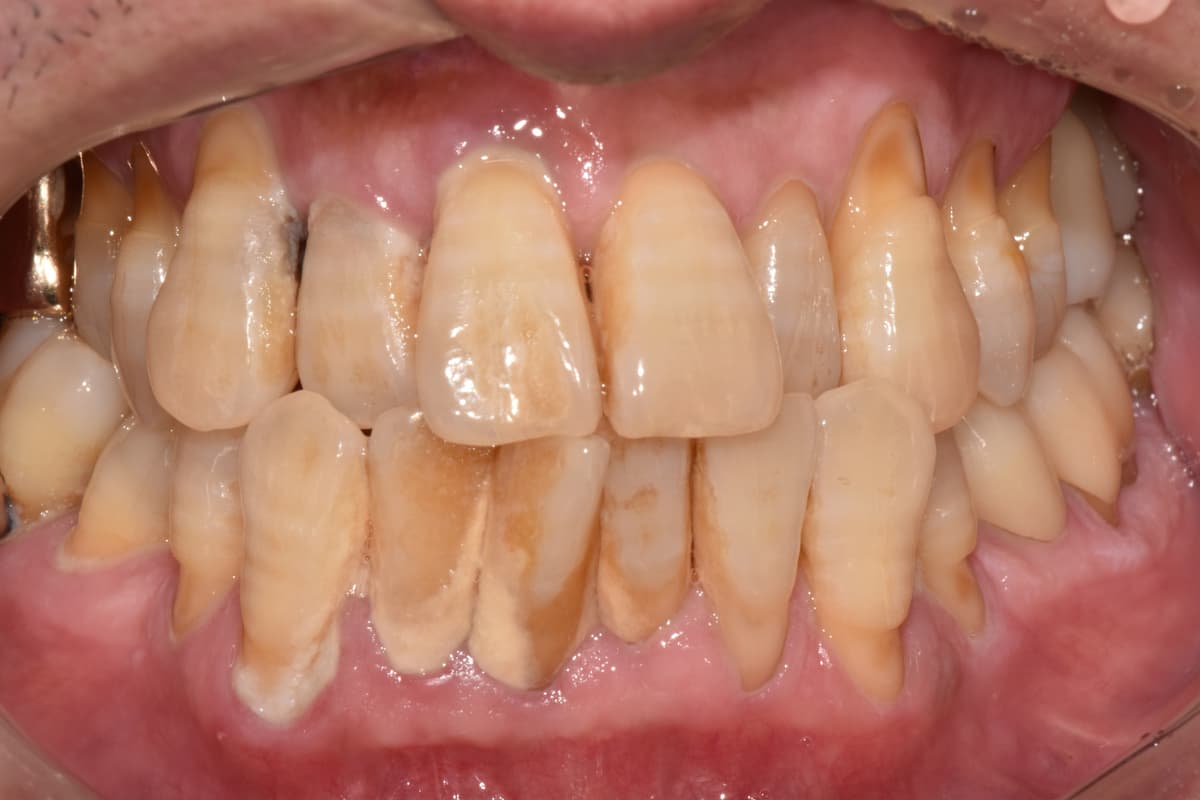

"Muntazam parvarish tufayli

50 yoshimda ham barcha tishlarim sog'lom"

Before

After

Tish toshi va milk yallig'lanishi og'ir bo'lgan holat

Muntazam scaling va parvarish orqali sog'lom holatda saqlanmoqda